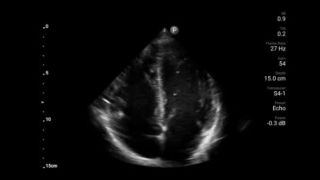

Congestief hartfalen is een groeiend probleem. Door echografie op uw praktijk te bieden, kan deze aandoening vroegtijdig worden ontdekt en de overlevingskansen aanzienlijk worden verbeterd.

Harttamponade vermomt zich als buikpijn

Beoordeling van de functie van het linkerventrikel